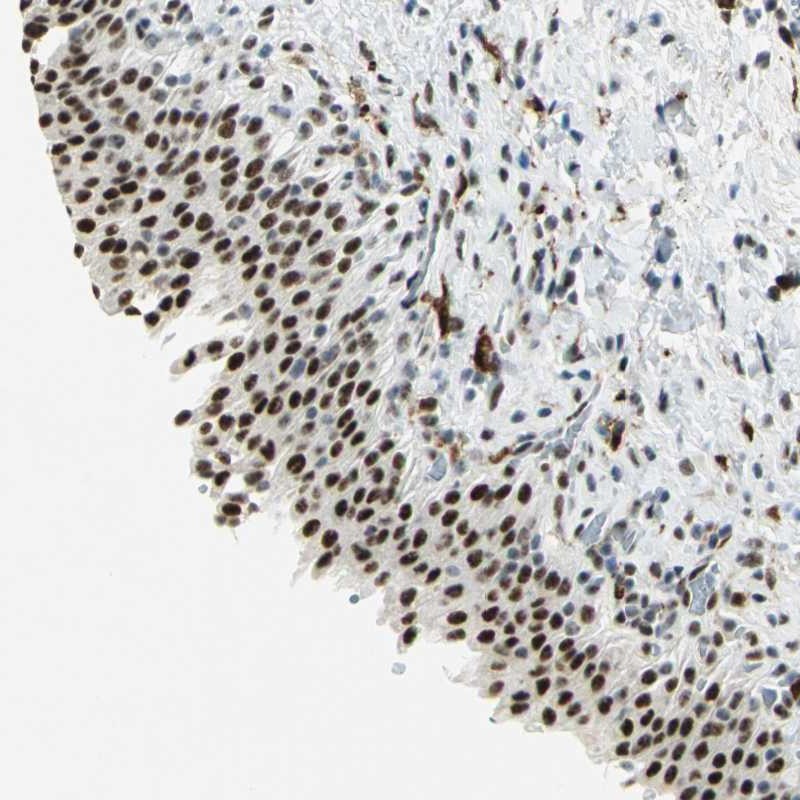

Immunohistochemical staining of human urinary bladder shows strong nuclear positivity in urothelial cells.